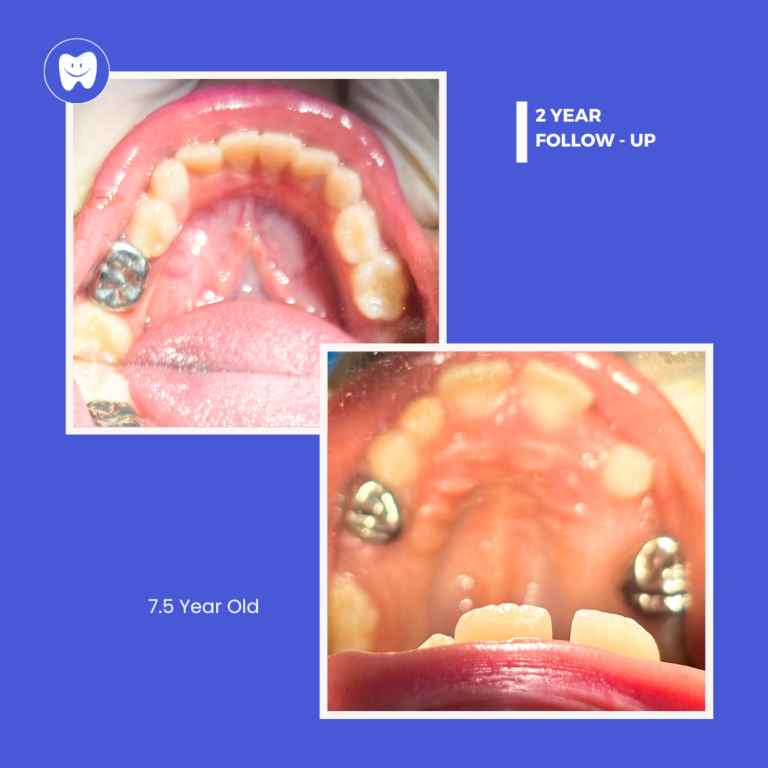

Post-Treatment Care

Aftercare instructions are given, and follow-up visits are scheduled to monitor progress and ensure the best outcome.

Improved Oral Health

Addressing multiple dental issues at once leads to better overall health and function.